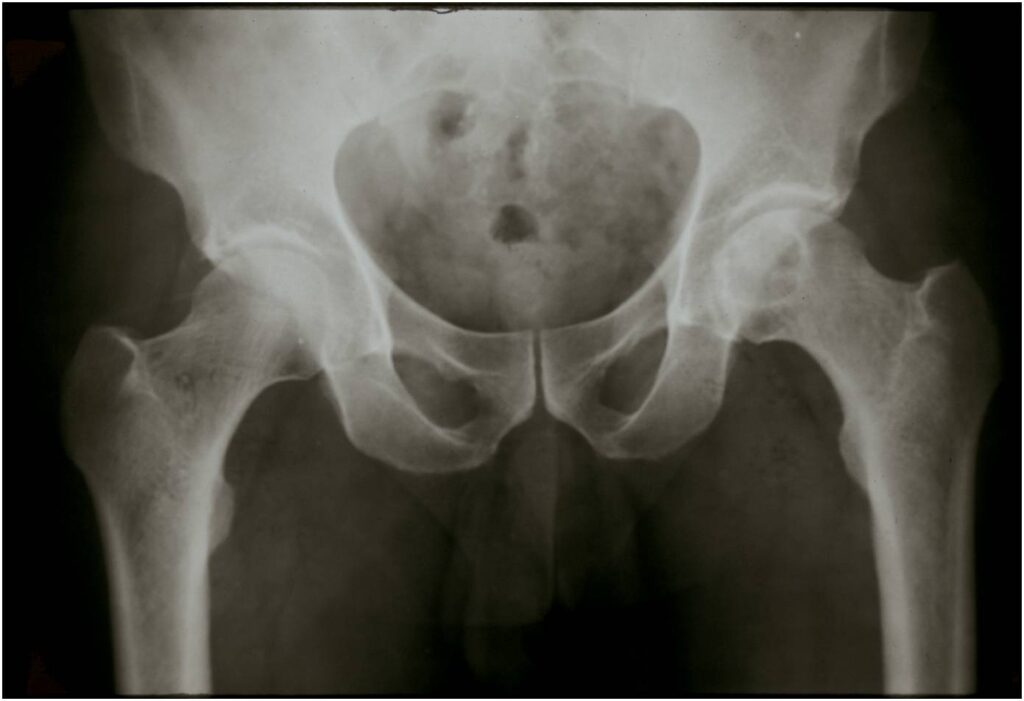

- Epiphyses of long bones

- Most commonly proximal femur, proximal humerus, distal femur, proximal tibia

- Usually osteolytic, expansile lesion

- May be focally calcified

- Often a sharp interface between tumor and surrounding bone

- Overlying cortex is usually thin, but intact